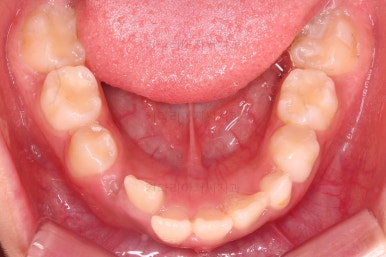

1. 초진

초진 시 입안의 모습입니다.

가장 눈에 띄는 건, 아랫니가 윗니보다 앞에 나와있는 부정교합인데요.

아래 앞니는 윗니의 뒤쪽에서 힘을 받기 좋은 구조로 되어있는데, 앞쪽에서 튀어나가 있으면 마모나 잇몸 손상이 많이 올 수 있습니다.